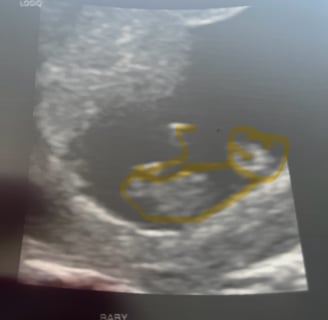

Managing Fatigue during the First Trimester of Pregnancy

Fatigue, nausea, and ligament changes during the first trimester of pregnancy might change how you homestead.

Being pregnant during the first trimester can be an exciting and challenging time. Your body is undergoing numerous changes, and it's important to prioritize your health and well-being.